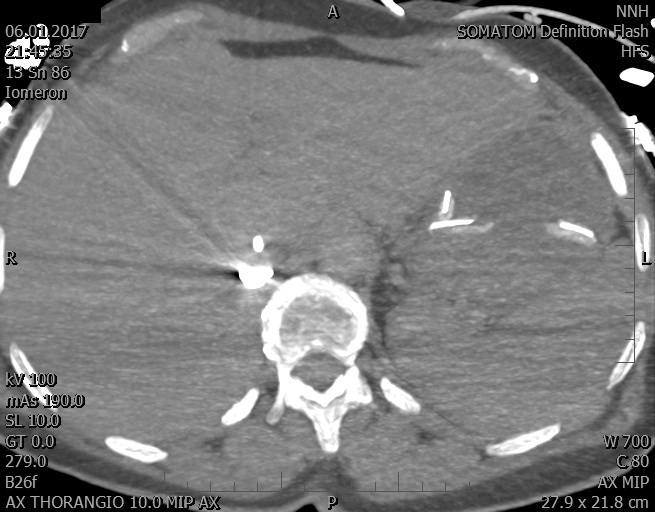

Video 2 - Echokardiograficky byla zjištěna těžká dysfunkce dilatační levé komory s nezvětšenou pravou komorou.Pro nejasnou příčinu zástavy jsme provedli i vyšetření výpočetní tomografií (CT), které vyloučilo plicní embolizaci (série 1 - soubory na konci článku). V den přijetí při přetrvávající oběhové nestabilitě byla nemocná opakovaně defibrilována pro fibrilaci komor se stabilizací rytmu po podání amiodaronu a mesocainu. Dle hemodynamických měření se jednalo o těžký kombinovaný šok. Vstupní laboratorní vyšetření bylo bez větších pozoruhodností. Posléze jsme doplnili anamnézu od příbuzných a zjistili, že pacientka užila do dvou hodin před srdeční zástavou první tabletu amoxicilinu na lehký respirační infekt. Při nevýtěžnosti vstupních vyšetření a nových anamnestických informacích jsme doplnili 14 hodin po kolapsu vyšetření koncentrace tryptázy v séru, která byla extrémně zvýšena (tabulka 2), což nás vedlo k podezření na anafylaxi.